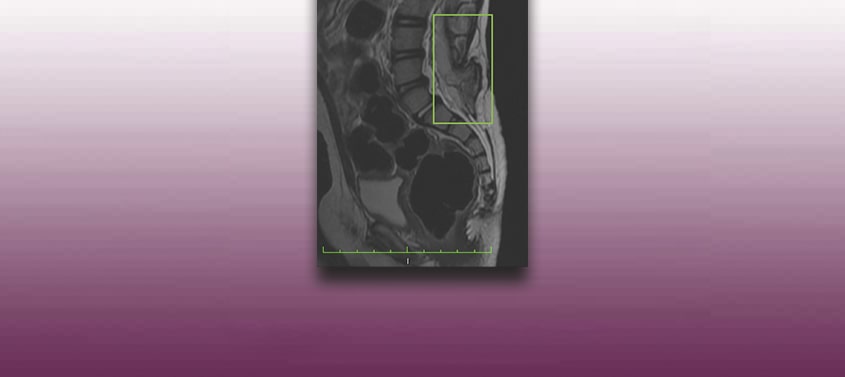

Medula presa com espinha bífida – meningocele ou mielomeningocele- ou Tethered Cord Syndrome

Última atualização: 04/03/2020, Dr. Miguel B. Royo Salvador, número de registro médico: 10389. Neurocirurgião e Neurologista. Definição Em condições normais, dentro do canal vertebral, a medula espinhal está unida somente pelos ligamentos denteados e pelo Filum terminale. Este último é um ligamento que une o cone medular às primeiras vértebras do cóccix. No entanto, […]